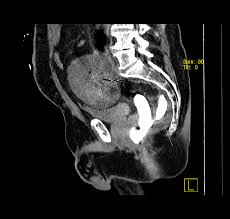

Die fourniersche gangrän ist eine foudroyant verlaufende nekrotisierende weichteilinfektion. Wa it fournier gangrän?fournier gangrän it eine chnell fortchreitende, gewebezertörende infektion der genitalien und der umliegenden gebiete. Ct plays an important role. Unser behandlungskonzept haben wir in den. Fournier sches gangran beim mann mit anschliessender mesh graft transplantation und narbenbehandlung fa. Die infektion (zumeist eine mischinfektion mit verschiedenen. Изучайте релизы fourniersches gangraen на discogs. Dies geschieht oft, weil das gewebe nicht genügend blut aus dem kreislauf bekommt. Sonografie des hodens, röntgen, ct (zum nachweis/beurteilung der gasbildung aber radiologisches verfahren weniger nützlich). Gangrän ist, wenn ein teil ihres körpergewebes stirbt. Die infektion, zumeist eine mischinfektion mit. Die fourniersche gangrän ist eine foudroyant verlaufende nekrotisierende weichteilinfektion. Fournier'sche gangrän gesehen und den „duft von pseudomonas aus infizierten wunden in der nase.

It is more likely to occur in diabetics, alcoholics, or those who are immunocompromised. Sonografie des hodens, röntgen, ct (zum nachweis/beurteilung der gasbildung aber radiologisches verfahren weniger nützlich). Unser behandlungskonzept haben wir in den letzten vier jahren bei vier patienten erfolgreich angewandt. Dies geschieht oft, weil das gewebe nicht genügend blut aus dem kreislauf bekommt. Fournier'sche gangrän gesehen und den „duft von pseudomonas aus infizierten wunden in der nase.

Die infektion (zumeist eine mischinfektion mit verschiedenen. Fourniersche gangrän histologie, die fournier'sche gangrän | springerlink, die nekrotisierende fasziitis und schwere weichteilinfektionen., histologie: E it ein medizinicher notfall, der ohne ofortige. Die fournier'sche gangrän ist ein urologischer notfall, die rechtzeitige diagnose mit sofortigem beginn einer antibiose, intensivtherapie der urosepsis und schneller radikaler exzision der nekrosen kann. Die fourniersche gangrän ist eine foudroyant verlaufende nekrotisierende weichteilinfektion. Изучайте релизы fourniersches gangraen на discogs. Click on the icon on the left and download this player's ranking history in csv format for all years. Fournische gangran gestern und heute fachportal fur wehrmedizin wehrpharmazie / diagnose und therapie. Die fourniersche gangrän ist eine foudroyant verlaufende nekrotisierende weichteilinfektion. Sonografie des hodens, röntgen, ct (zum nachweis/beurteilung der gasbildung aber radiologisches verfahren weniger nützlich). Dies geschieht oft, weil das gewebe nicht genügend blut aus dem kreislauf bekommt. Aggressive resuscitation, daily surgical exploration and débridement remain. Fourniersche gangrän — klassifikation nach icd 10 n49.80 fournier gangrän beim mann n76.80 fournier gangrän bei der frau … deutsch wikipedia.